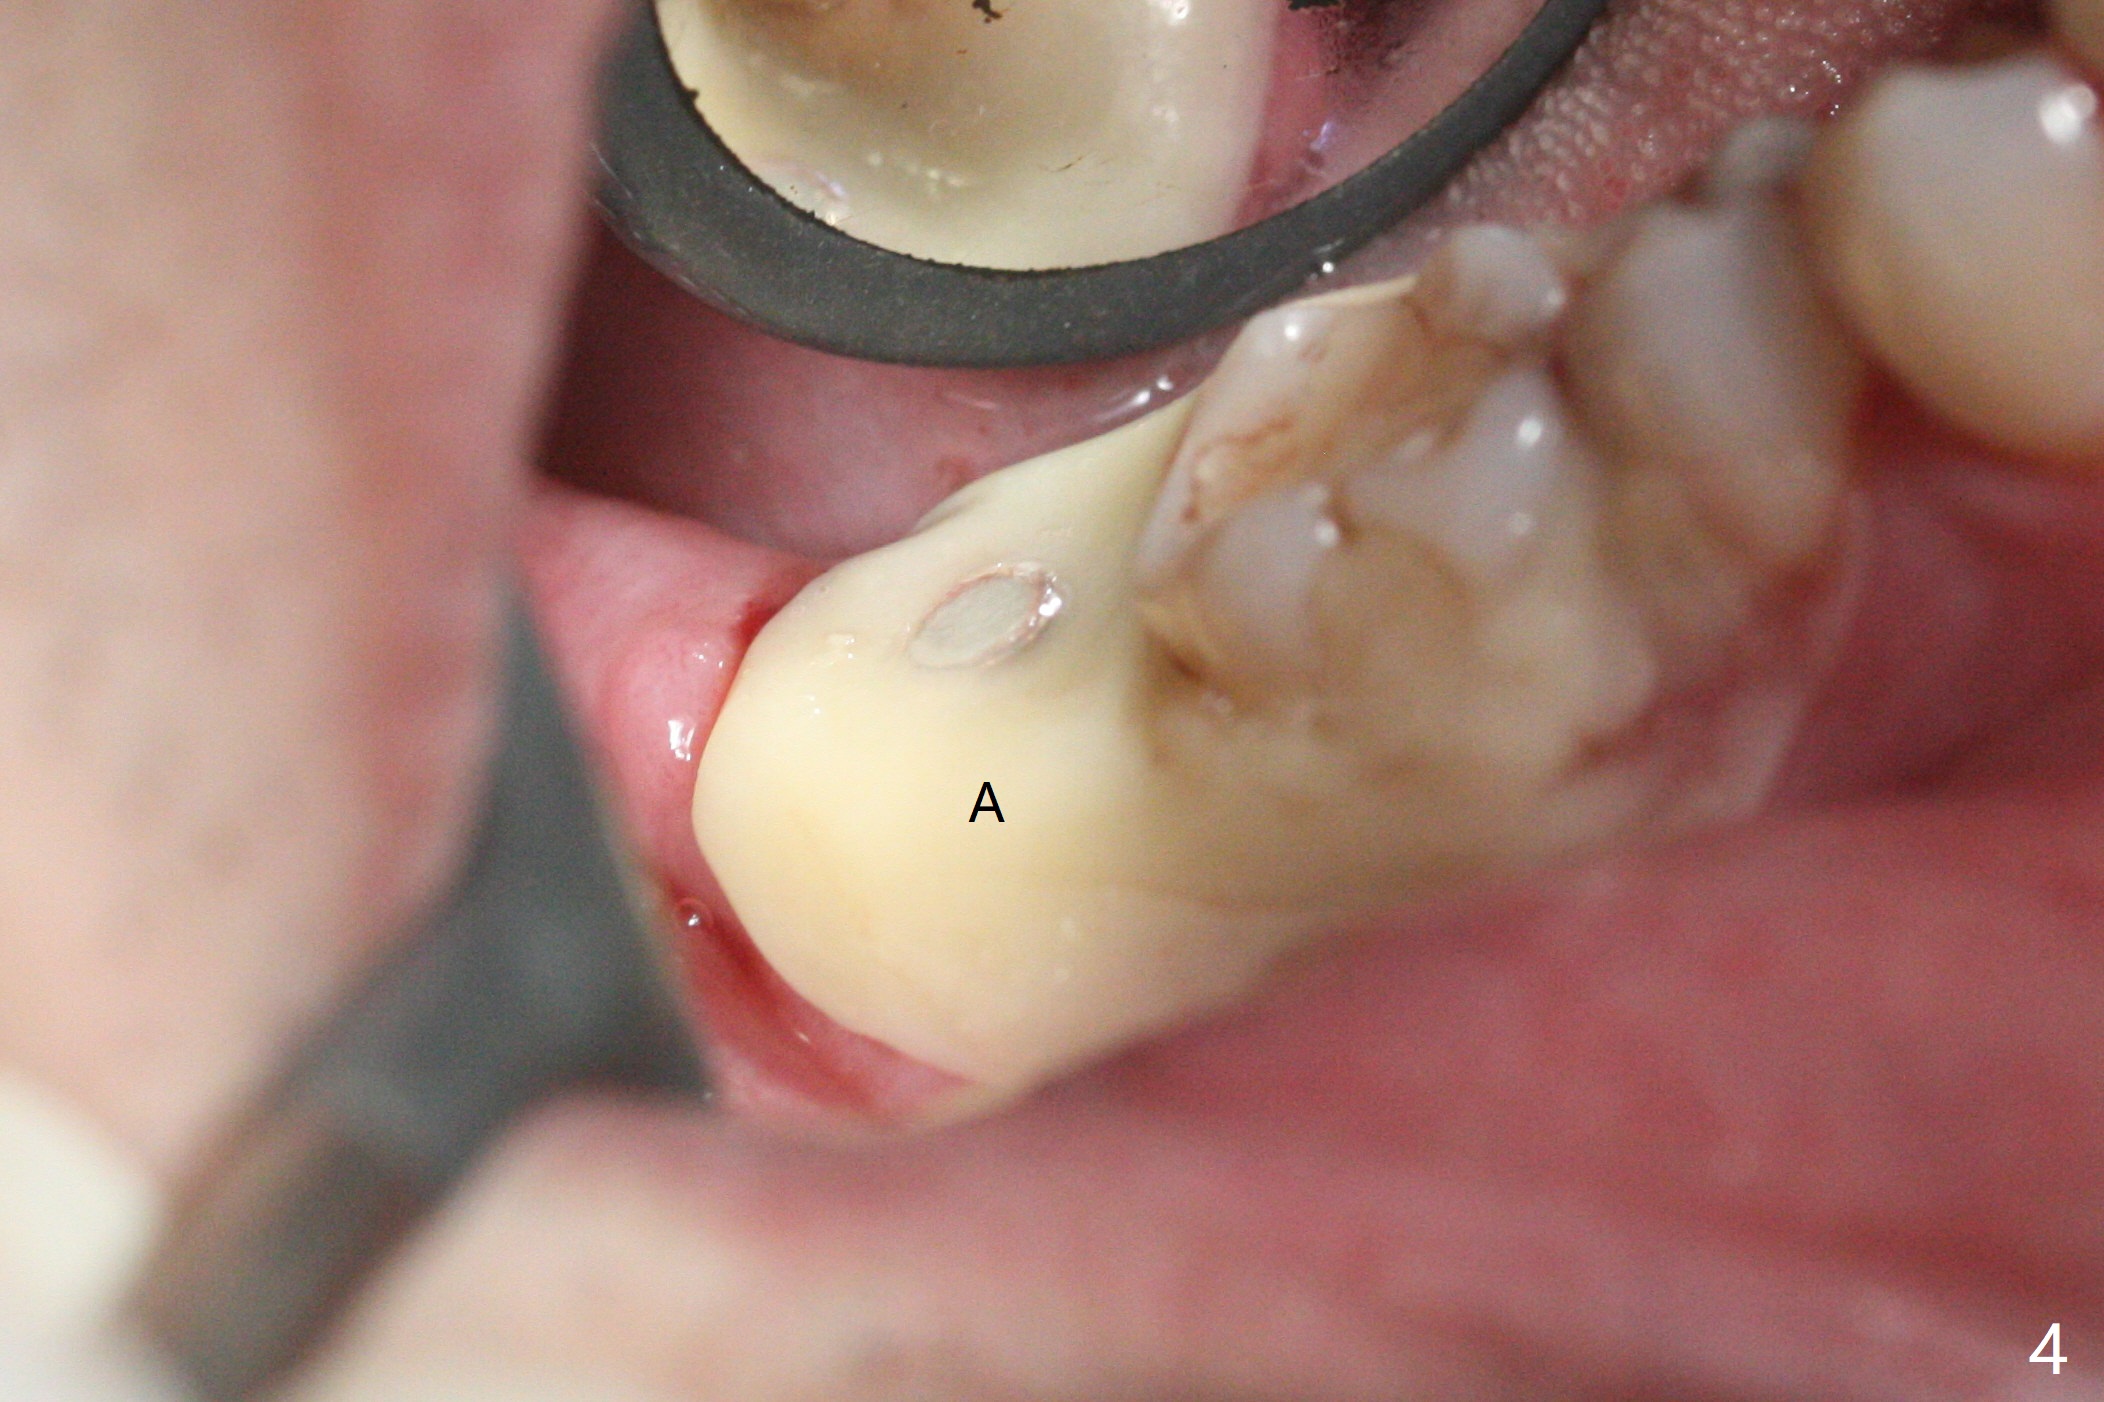

右下七5x11.5毫米植体导板植入根尖骨质大约2-3毫米(图一),扭力~50 Ncm,即使发生骨坏死,不会产生植体周围炎,最坏植体松动脱落。放置基台后,植入大量粘性骨粉(图二:*),覆盖PRF(图三);如果使用临时牙冠关闭牙槽窝,牙冠与龈缘(箭头)接触不紧,使用水牙线冲洗,骨粉流失严重。所以采纳树脂敷料(图四:A),后者边缘至少覆盖牙槽窝口1-2毫米,一周复查,及时关闭术后牙龈退缩所造成的漏洞。其实病人术后第二天回来,敷料脱落,理由:远中无牙,基台短(图五)。Return to Prevent Molar Periimplantitis (Protocols, Table) Protect Graft Torque 第一磨牙即种 Xin Wei, DDS, PhD, MS 1st edition 04/27/2021, last revision 04/29/2021